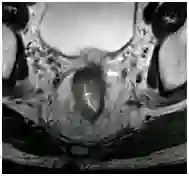

MRI评估CRM同样存在缺点,直肠内对比时因肠壁扩张可能干扰肿瘤与直肠系膜筋膜距离的测定。直肠系膜筋膜只适用于腹腔外,因此CRM只适用于腹膜返折下肿瘤,如肿瘤位于上段直肠伴腹膜返折受累时为T4a,CRM阴性。肿瘤距离直肠系膜筋膜<1mm时报告切缘阳性,肿瘤沉积、EMVI或直肠系膜淋巴结也应报告切缘阳性(图10)。直肠系膜筋膜距下段直肠前壁很近,易被下位直肠癌累及或CRM阳性(图11)。CRM距离应测量肿瘤脂肪交界至直肠系膜筋膜的最短距离。

图10  61岁男性直肠癌,轴位T2加权像显示直肠肿物(星号),左侧直肠系膜EMVI(箭头),右侧直肠系膜淋巴结受累(长箭头),CRM侵犯。

图11  61岁男性直肠癌,轴位T2加权像显示直肠前壁锯齿状肿瘤,CRM侵犯(长箭头)。直肠前壁与直肠系膜筋膜非常接近,前壁直肠肿瘤CRM 阳性可能性较高。